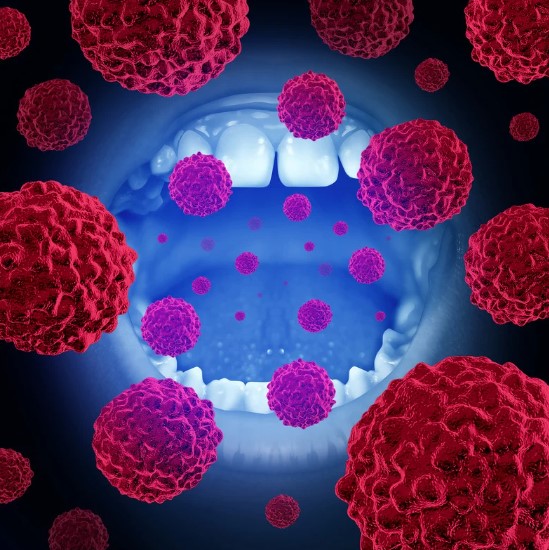

Corrección de lesiones quísticas y tumorales en la cavidad oral

Las lesiones quísticas o tumorales en la cavidad oral pueden aparecer por diversas causas, desde infecciones hasta alteraciones celulares. Estos quistes o tumores, aunque no siempre son malignos, deben ser tratados con cirugía para prevenir complicaciones como infecciones, desplazamiento de dientes o daño a estructuras cercanas.

El tratamiento quirúrgico consiste en la eliminación completa de la lesión y, en algunos casos, la reconstrucción del área afectada. Es un procedimiento delicado que requiere un diagnóstico preciso y seguimiento para garantizar la salud del paciente.

Quistes o lesiones en la cavidad oral

Estas anomalías, si no se tratan, pueden crecer y comprometer la estructura ósea o los tejidos blandos de la boca.